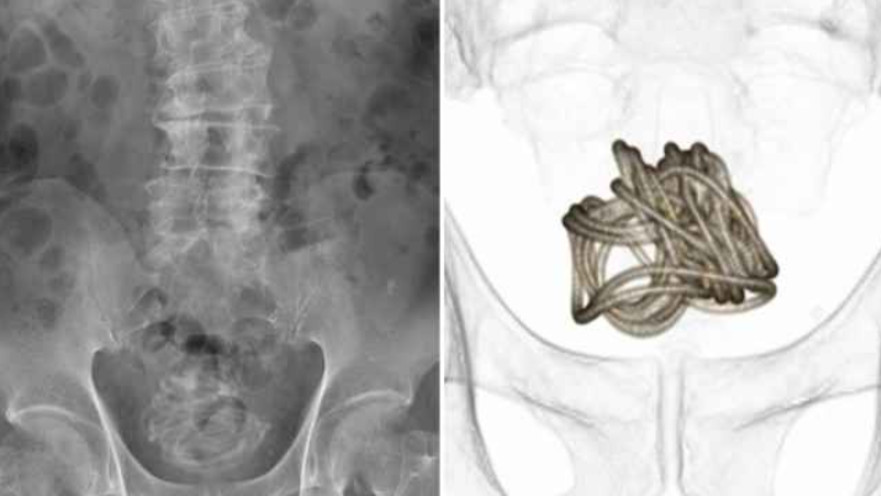

הצוות הרפואי נאלץ לחלץ את החבל דרך חתך שנעשה בבטנו של בן ה-79. למרבה המזל, האיש החלים במהירות ולא סבל מפציעות או מסיבוכים.